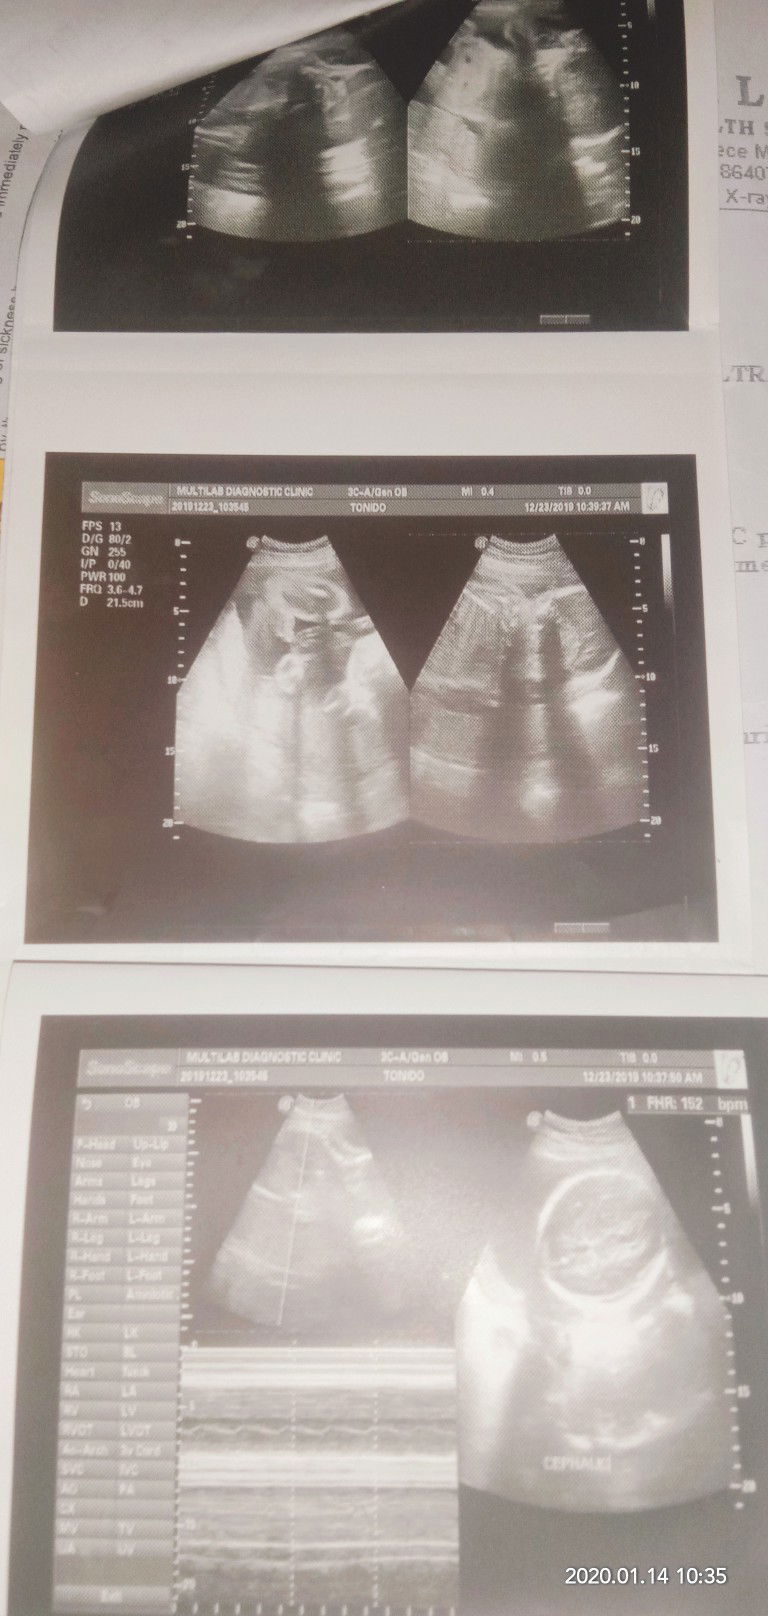

ultrasound result

Mga mommies may nag kakamali ba sa result ng ultrasound?? Very sure po kse ako sa last first day of menstruation ko.. Sa due date calculator ko po lumalabas march 22 ung EDD ko.. Ganun din kpag nag papacheck up ako sa clinic.. Pero ang lumabas sa ultrasound ko is march 5. Tapos sabi sakin ng sonologist na nag ultra sound hindi nia raw mkita kung isa lang daw ung baby sa tiyan ko.. Pero lalaki raw ung baby ko. Nag pa ultasound po ako 6 months.. Sabi niya dapat nag pa ultra sound daw po ako ng mas maaga.. Tanong ko lang din po kung hindi ba nila mkikita kung isa lng ung nasa loob? Diba mas mkikita nila un kse malaki na ung baby sa loob ng tiyan? Then sabi niya sakin mag pa check daw ako sa obegyne baka raw kse kambal hindi sya sigurado dahil 6bmonths ung tyan ko pra nadaw ka buwanan ko na. 33 cms. Salamat po sa mga sasagot..?